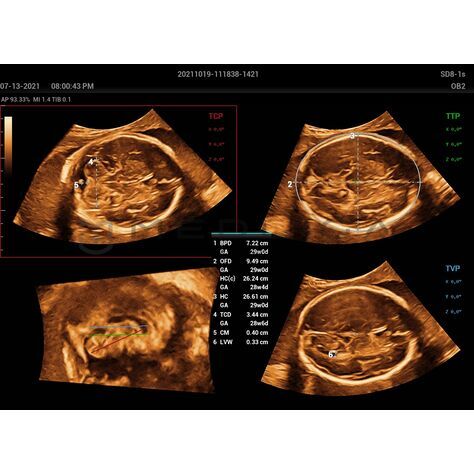

• Полностью автоматическое распознавание срезов, 4 стандартных среза ЦНС

• Высокоточные измерения, 6 часто используемых фотометрических параметра

• BPD — обмер и вычисление бипариентального размера головы

• HC — окружность головы

• OFD — лобно-затылочный размер головы

• TCD — межполушарный размер мозжечка

• LVW — ширина боковых желудочков